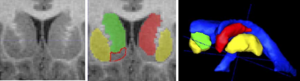

Publication: PLoS One. 2015 Dec 29;10(12):e0145493. PMID: 26713760 | PDF Authors: Esterhammer R, Seppi K, Reiter E, Pinter B, Mueller C, Kremser C, Zitzelsberger T, Nocker M, Scherfler C, Poewe W, Schocke M. Institution: Department of Radiology, University Hospital, Innsbruck Medical University, Innsbruck, Austria. Background/Purpose: The purpose of the present study was to evaluate the potential of multimodal MR imaging including mean diffusivity (MD), fractional anisotropy (FA), relaxation rates R2 and R2* to detect disease specific alterations in Parkinson's Disease (PD). We enrolled 82 PD patients (PD-all) with varying disease durations (≤5 years: PD≤5, n = 43; >5 years: PD>5, n = 39) and 38 matched healthy controls (HC), receiving diffusion tensor imaging as well as R2 and R2* relaxometry calculated from multi-echo T2*-weighted and dual-echo TSE imaging, respectively. ROIs were drawn to delineate caudate nucleus (CN), putamen (PU), globus pallidus (GP) and substantia nigra (SN) on the co-registered maps. The SN was divided in 3 descending levels (SL 1-3). The most significant parameters were used for a flexible discrimination analysis (FDA) in a training collective consisting of 25 randomized subjects from each group in order to predict the classification of remaining subjects. PD-all showed significant increases in MD, R2 and R2* within SN and its subregions as well as in MD and R2* within different basal ganglia regions. Compared to the HC group, the PD≤5 and the PD>5 group showed significant MD increases within the SN and its lower two subregions, while the PD≤5 group exhibited significant increases in R2 and R2* within SN and its subregions, and tended to elevation within the basal ganglia. The PD>5 group had significantly increased MD in PU and GP, whereas the PD≤5 group presented normal MD within the basal ganglia. FDA achieved right classification in 84% of study participants. Micro-structural damage affects primarily the SN of PD patients and in later disease stages the basal ganglia. Iron contents of PU, GP and SN are increased at early disease stages of PD. Funding:

The regions-of-interest (ROIs) were manually drawn by an experienced radiologist by using the b 1000 images, averaged for all measured directions, the FA maps and the proton-density weighted images. For that purpose, the maps of ADC, FA, R2 and R2* as well as the proton-density weighted images were first co-registered. The ROIs were segmented by syncing the b 1000 images, averaged for all measured directions, the FA maps and the proton-density weighted images in ImageJ. The ROIs were stored in the ROI manager and transferred to the co-registered maps. The segmented brain regions were highlighted in different colors: CN—black; PU—red; GP—green; TH—white; SN—blue; CC—cyan. The diffusion-weighted images, the R2 and R2*-weighted maps were transferred to the 3D Slicer software in order to co-register the R2 and the R2* maps as well as the MD and the FA maps |